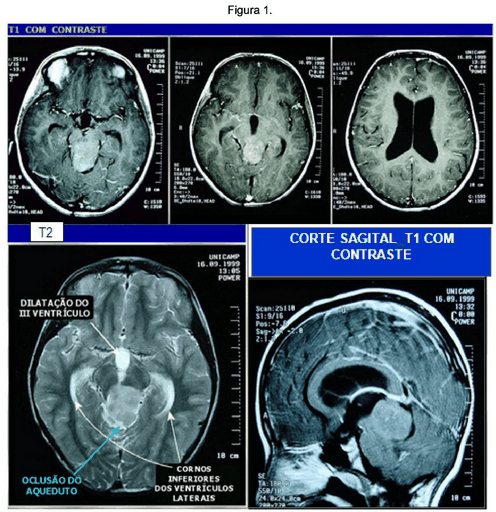

Paciente Feminina de 9 anos. Desde os 5 anos tem epilepsia e diagnóstico de tumor cerebral. Feita biópsia, material inconclusivo. Sete meses após a cirurgia continuava com piora progressiva da cefaléia e crises epilépticas esporádicas. Atualmente apresenta déficit cognitivo e hipoacusia E. As imagens da ressonância magnética e o laudo estão apresentados nas Figuras 1 e 2, e no Texto 1, respectivamente.

Ressonância Magnética de Crânio. Cortes Axiais T1 com contraste e T2; Corte Sagital com contrate.

Fonte: UNICAMP. Anatomopatológico.

Disponível em: http://anatpat.unicamp.br'radastropilo2.html.Acessado em 21/09/2013.

O Laudo da Ressonância Magnética: Os cortes axiais mostram lesão bem delimitada e aproximadamente esférica no mesencéfalo, ocupando quase todo o tegmento e a placa quadrigêmea, com obliteração do aqueduto de Sylvius e hidrocefalia supratentorial (afetando o III ventrículo e os laterais). A lesão tem aspecto expansivo e comprime o vermis superior.

Nos cortes pesados em T2 a lesão mostra-se predominantemente homogênea e com hipersinal, indicando tratar-se de uma lesão hidratada. Não há componente cístico. Os cortes sagitais, T1 com contraste mostram Tumor Sólido, bem delimitado, originado na placa quadrigêmea; comprime anteriormente o mesencéfalo e posteriormente a porção anterior do vermis. Impregna-se de forma difusa e levemente heterogênea. O halo de liquor em volta da lesão na cisterna cerebelar superior demonstra que o tumor provém do mesencéfalo. Os cortes coronais T1 em contraste mostram que o tumor é originado na placa quadrigêmea deforma o III ventrículo (Situa-se no nível da incisura do tentório e eleva a pineal, mas não a invade).